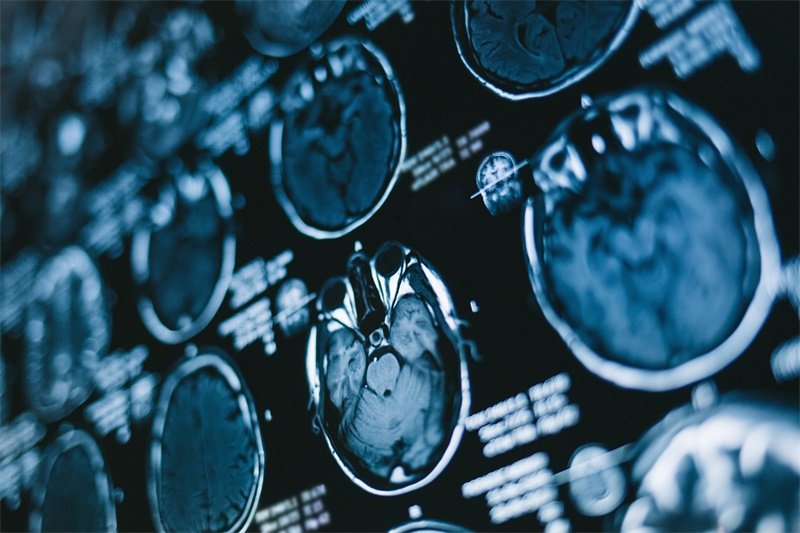

什么是静止性脑积水?有哪些症状?在神经外科门诊,常会遇到这样一类患者:他们的头颅影像显示脑室扩大,却没有头痛、呕吐等典型高颅压症状,日常生活几乎不受影响——这种看似矛盾的状态,正是静止性脑积水的特殊表现。这种特殊类型的脑积水,被2025年《脑外伤后脑积水最新治疗指南》定义为:脑脊液异常积聚停止,脑室系统不再进行性增大,相关临床表现也无进展的稳定状态。中国脑积水联盟的多中心数据显示,在脑外伤后脑积水患者中,约18%会发展为静止性脑积水,其中60岁以上人群占比高达62%。

诊断标准的四维验证

影像学稳定

•Evans指数恒定:差值<0.03(间隔6个月两次测量)

•脑沟宽度维持:额叶皮层厚度变幅≤0.5mm

•DTI白质完整性:FA值>0.25(胼胝体压部)